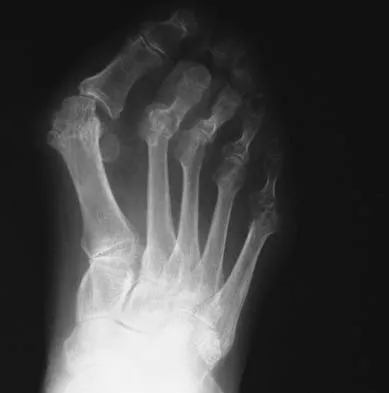

A 19-year-old woman has had a painful prominence on the lateral border of her fifth metatarsal head since she was a young girl. Nonsurgical management, including the use of a wide toe box shoe, has failed to provide relief. Examination reveals a callus over the lateral prominence and on the plantar portion as well. A clinical photograph and a radiograph are shown in Figures 34a and 34b. Treatment should consist of

Explanation

The type of deformity described is a type 2 bunionette. There is often a congenital component to this deformity. The bowing of the fifth shaft differentiates a large intermetatarsal angle from a type 3 deformity. A distal chevron osteotomy corrects 1 degree in the intermetatarsal angle for every 1-mm shift. Because of limitations in the width of the fifth metatarsal neck, the allowable shift is generally 3 to 4 mm. This shift will not compensate for the large intermetatarsal angle. The floating osteotomy has a high rate of delayed union/nonunion and a low satisfaction rate. Metatarsal head excision has a high complication rate, including severe shortening, transfer metatarsalgia, stiffness, and pain. A more proximal procedure is necessary to correct the large intermetatarsal angle and the lateral bowing. The osteotomy of choice is a diaphyseal shaft osteotomy. Because this patient has a plantar callosity and a lateral callosity, the osteotomy is angled superiorly to elevate the fifth shaft with the shift, eliminating overload of the plantar metatarsal head and subsequent callus formation. Shereff MJ, Yang QM, Kummer FJ, Frey CC, Greenidge N: Vascular anatomy of the fifth metatarsal. Foot Ankle 1991;11:350-353. Coughlin MJ: Treatment of bunionette deformity with longitudinal diaphyseal osteotomy with distal soft tissue repair. Foot Ankle 1991;11:195-203.